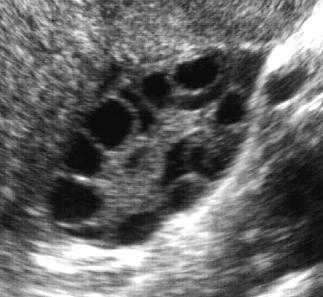

Ultrasonda yumurtalıkta hastalığa özgü 2-9 mm çapını geçmeyen bir çok sayıda kist ile ovulasyon yani yumurtlamanın olmaması izlenir. Yumurtlamanın olmamasına "anovulasyon" denir.

Ayrıca yumurtalıkların hacmi de normale göre artmıştır, yani yumurtalıklar normalden daha iri görünüdedir.

Aşağıdaki ultrason görünümlerinden soldaki bir normal overe aitken, sağdaki polikistik görünümdeki bir overe (yumurtalığa) aittir.